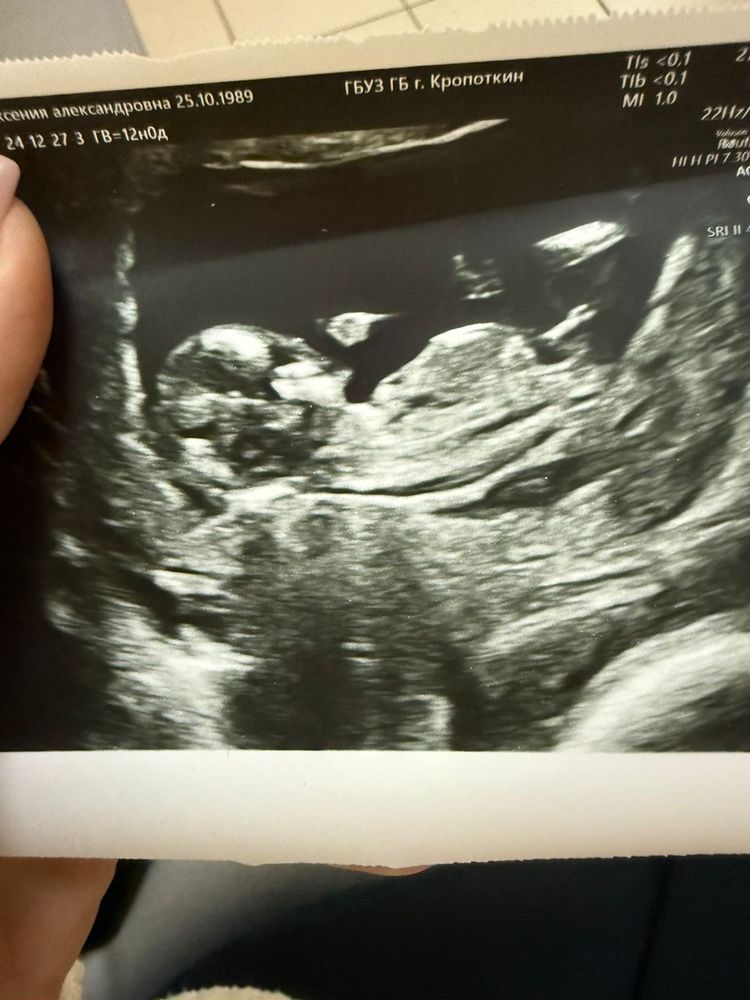

Как думаете какой пол?( не мое фото)

Я кучу бугорков пересмотрела 😁, это девочка💗

Яна, оказался мальчик)

Девочка

Девчушка вроде 😁